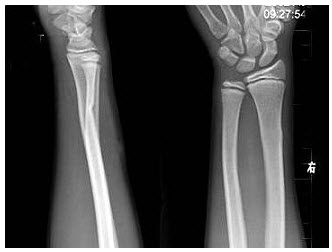

87、单项选择题

男,37岁,右手腕部外伤1.5小时,右腕部肿痛。根据右腕关节正侧位片,应诊断为()

A.Barton骨折

B.Colles骨折

C.Smith骨折

D.Monteggia骨折

E.Bennett骨折